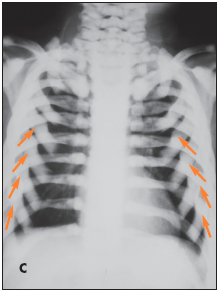

The child has osteopetrosis. The radiographs show diffuse osteosclerosis and dramatically increased bone density throughout the axial and appendicular skeleton. There is diffuse bone sclerosis in the hands with widening of the distal radial metaphyses (A, arrows) and a "bone-within-a-bone appearance"--typical of osteopetrosis--in virtually all the metacarpals and phalanges. Bone sclerosis is also apparent in the feet; the bone-within-a-bone appearance is most prominent in the metatarsals (B, arrows). A chest radiograph demonstrates diffuse bone sclerosis and numerous old fractures of the anterolateral ribs bilaterally (C, arrows).